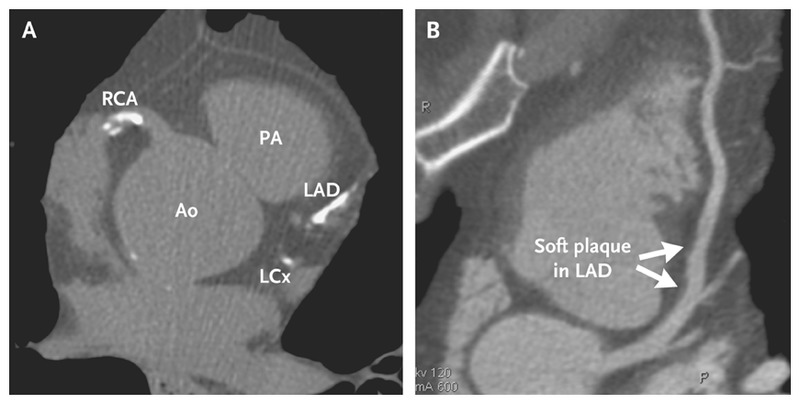

سی تی آنژیوگرافی قلب

سی تی آنژیو چیست؟